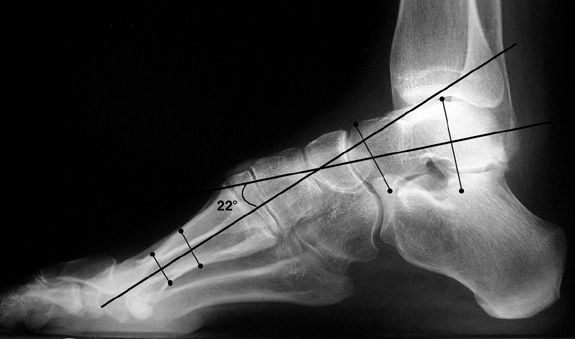

Pes Cavus Radiology Reference Article Radiopaedia Org